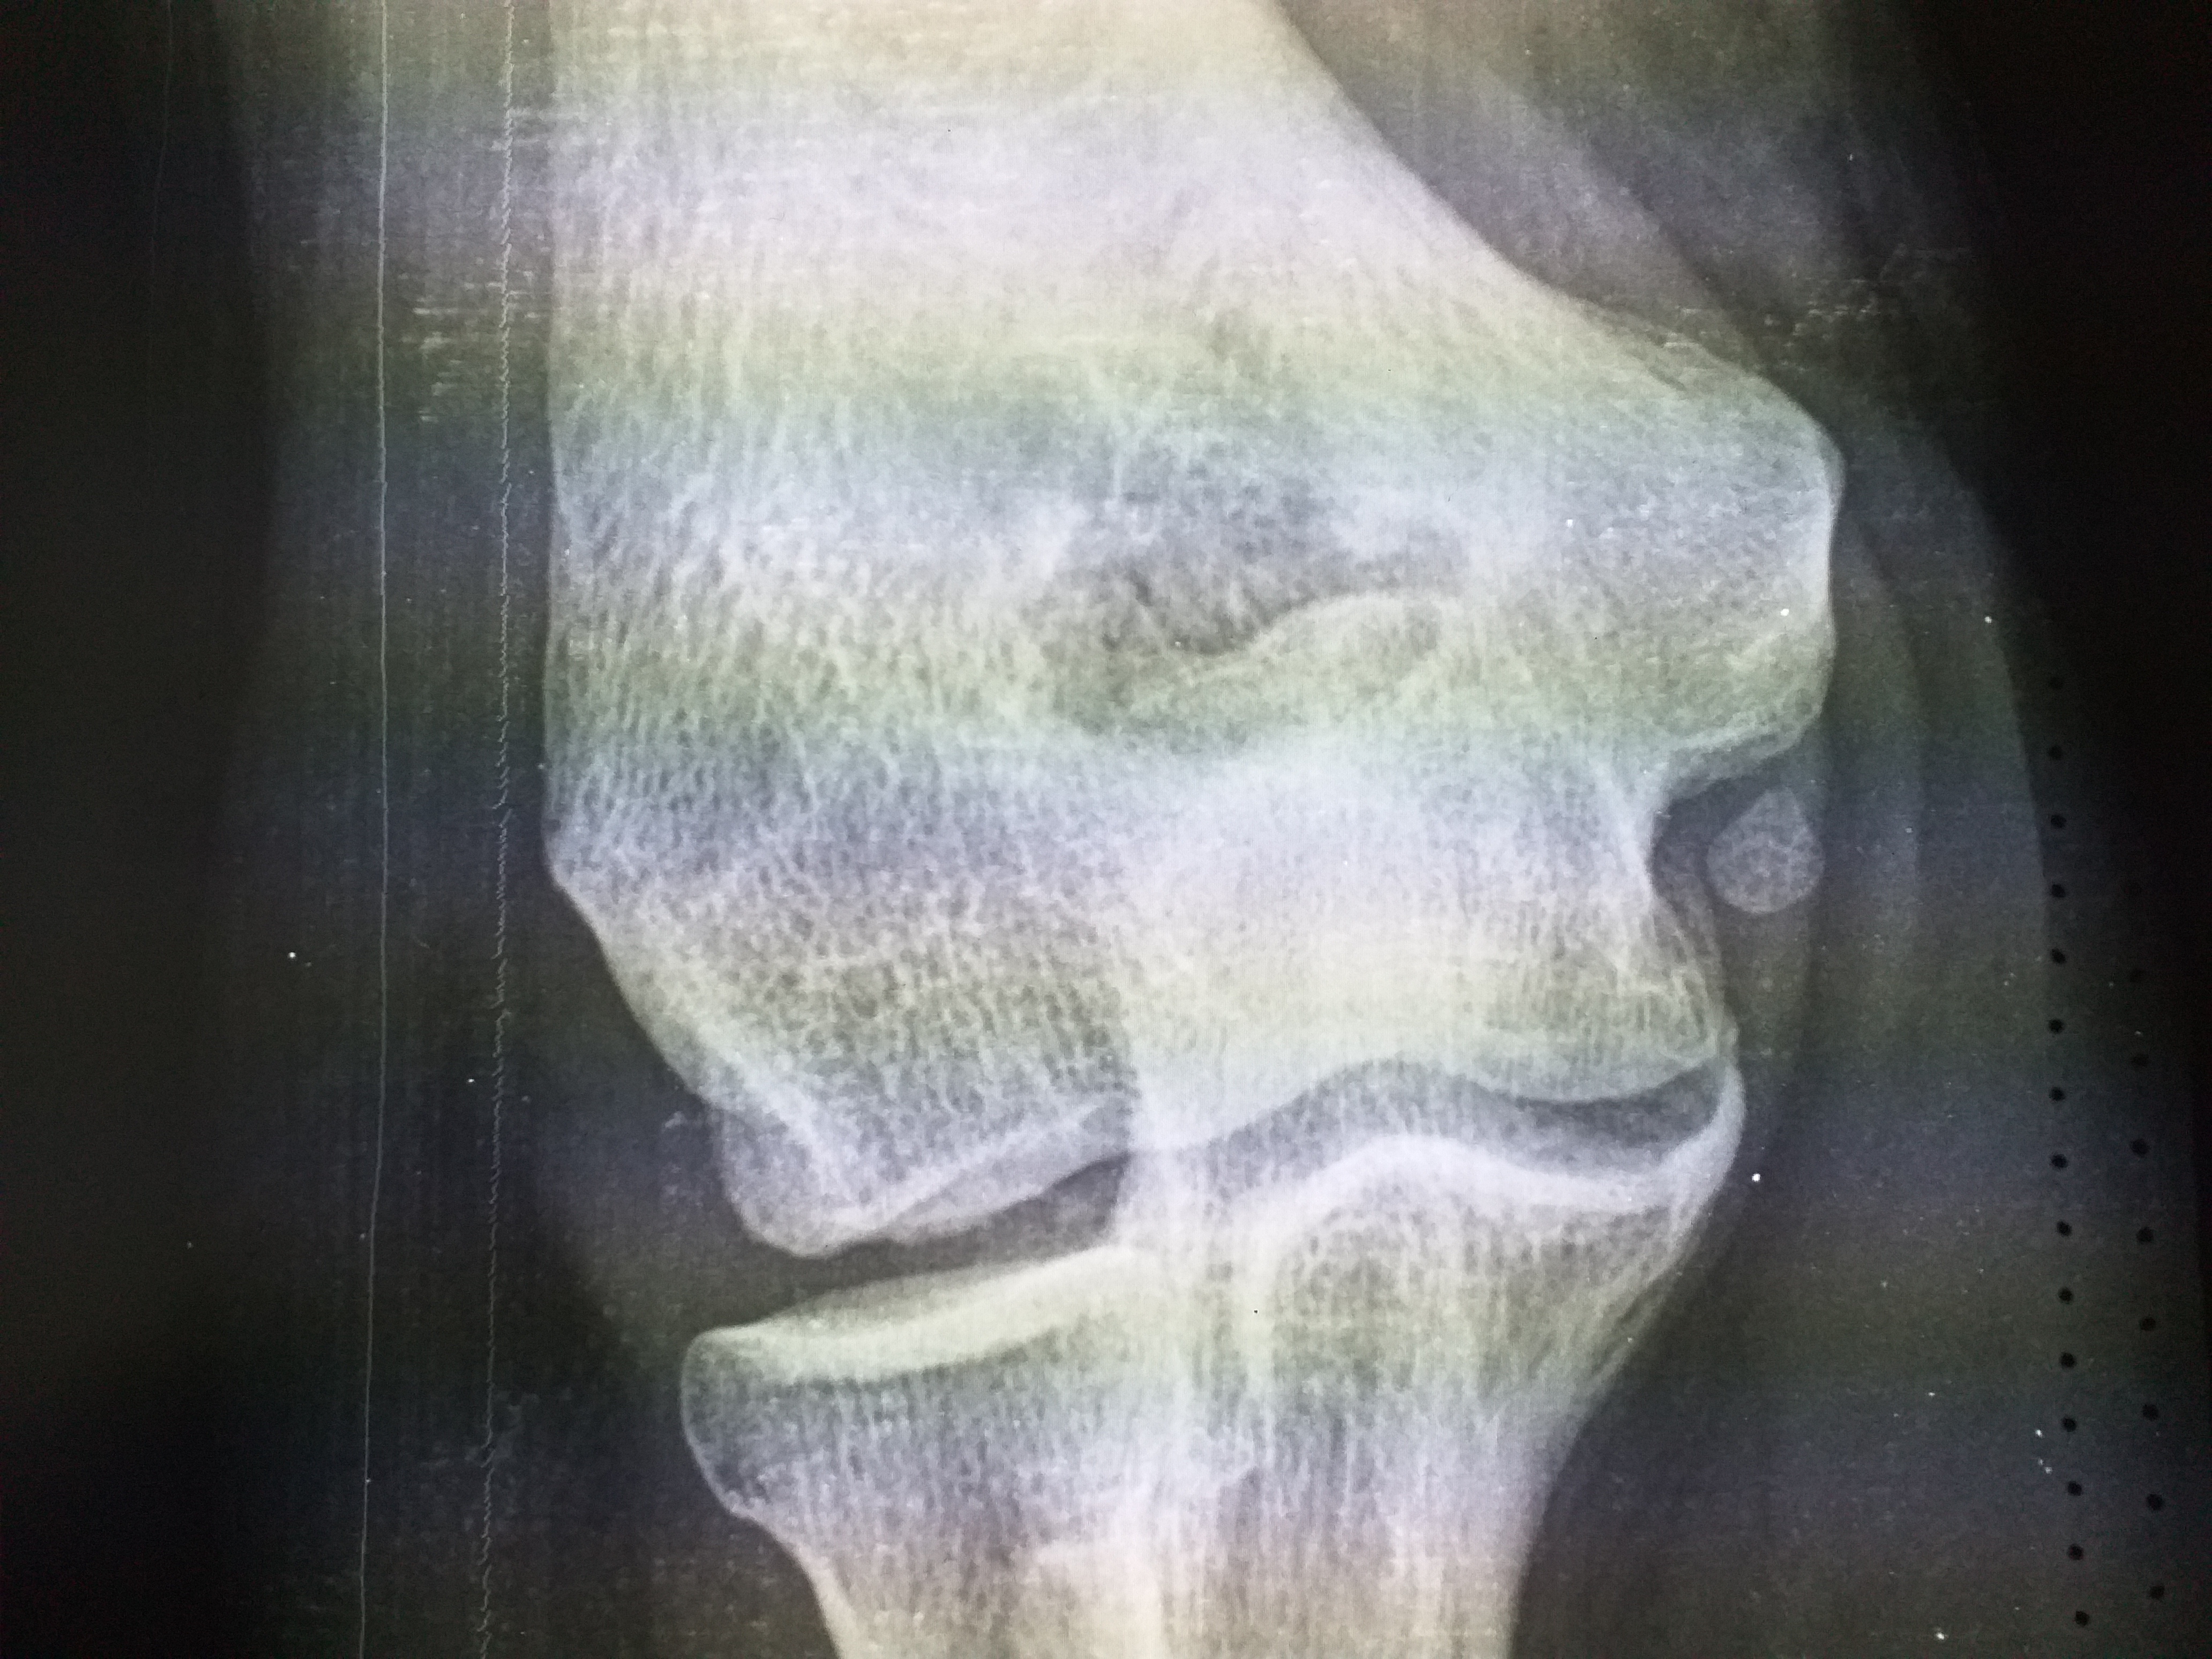

109. Локтевой сустав

Мужчина 1970 г р. Тренер по баскетболу. В течении месяца болит правый локтевой сутав в покое,при нашрузках боли интенсивнее. Объем движений сохранен,отека и синяков не видно. Тоавмы отрицает. Коллеги...

Тип: Клиническое наблюдение

Область: Скелетно-мышечная система

Модальность: Rg

Дата: 23.11.2022 - 08:20